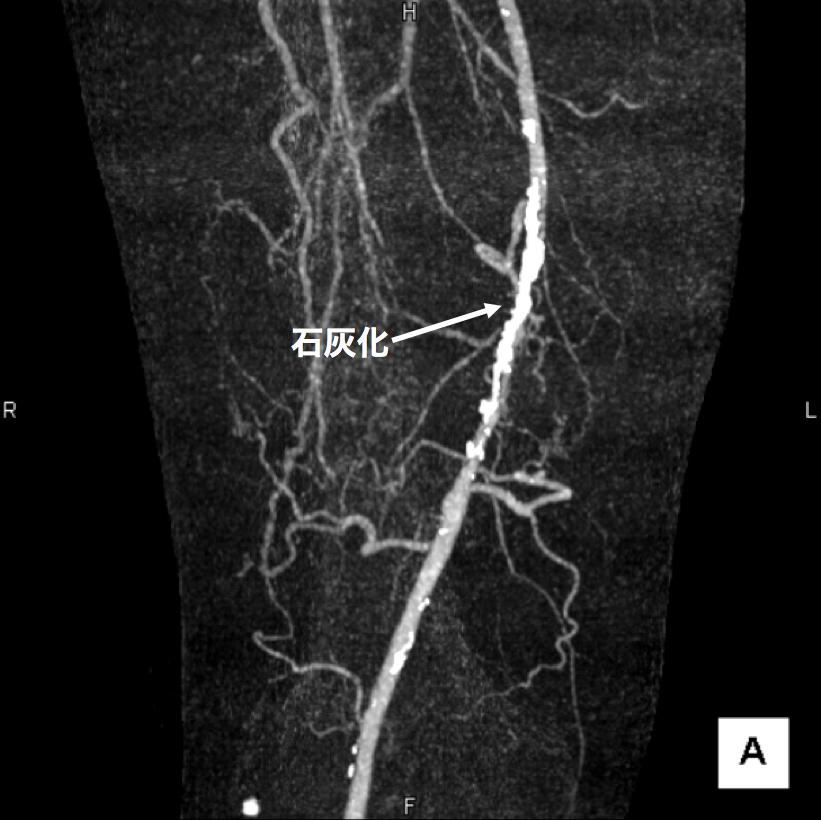

3、造影CT検査 造影剤を点滴しながらCTを撮像することで、血液の流れ、血管の状態などを把握します。情報量が多く治療方針を決定する場合に役立つので当院では特に力を入れている検査です。(図2、3、4)

図2

この画像は血管の立体的な走行の把握に有用です。

右足大腿部の血管に強い石灰化(動脈硬化の変化)があります。